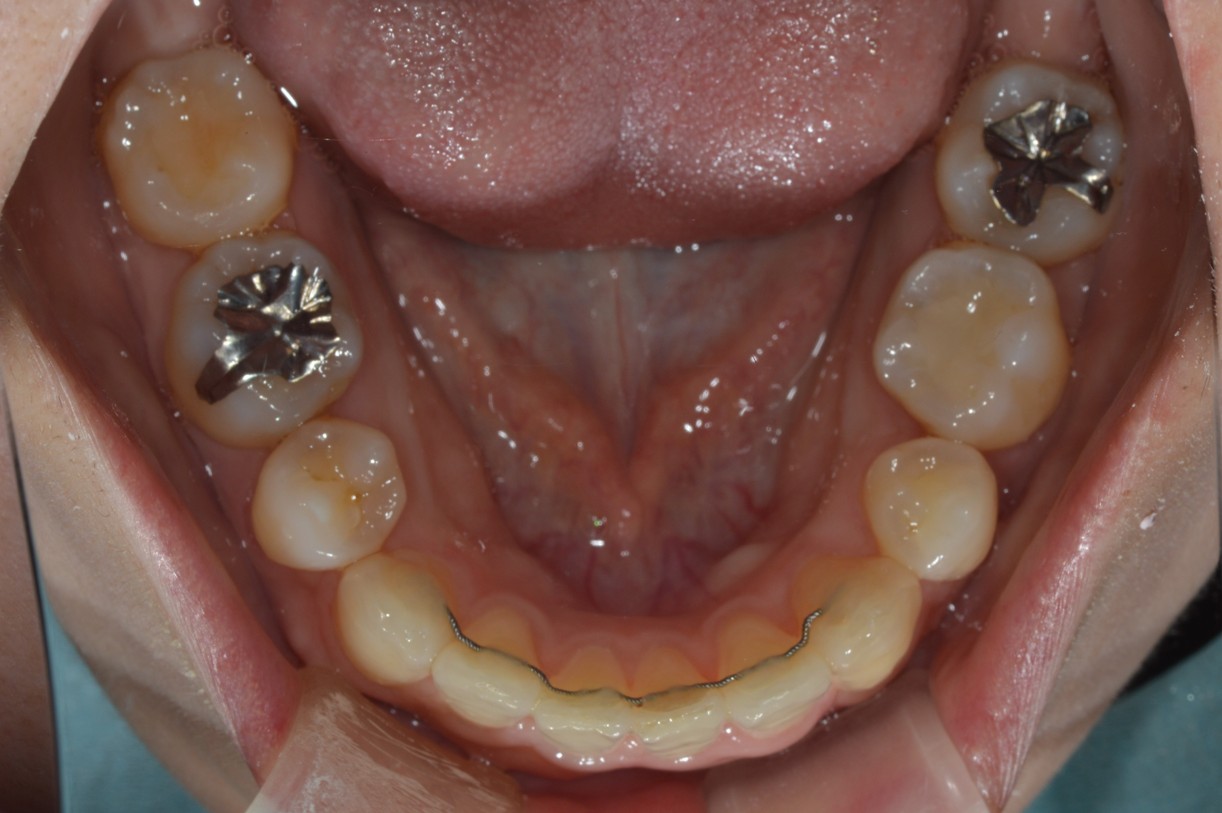

症例2

| 項目 | 詳細 |

|---|---|

| 患者様データ | 30代 女性 |

| 来院時の主訴 | 「右上の、内側に生えている歯が邪魔。」 |

| 矯正法 | 上の歯2本、下の歯2本、親知らず3本を抜歯しての矯正 |

| 通院期間 | 3年6ヶ月 |

| 治療費 | 総額:1,230,000円(税抜) 【内訳】 精密検査50,000円、メタルワイヤー矯正800,000円、月に1度の調整料5,000円、後戻り防止のリテーナー35,000円×2 |

| リスクと副作用 |

①歯を動かす事による痛みがあります。また、装置に慣れるまでは、口内炎ができやすいです。 ②歯肉が退縮するリスクがあります。装置が全ての歯に付くので、ハミガキが難しくなります。 ③長期的なメインテナンスが必要 |

| ここがこだわりのポイント!☝ | こちらの患者様は上の歯が1本内側に生えていましたが、奥歯の噛み合わせの方が問題でした。ハサミ状咬合といい、奥歯が極端に外側に向いており、下の歯と噛み合っていない状態でした。ハサミ状咬合は長期的にみると、前歯に大きな負担がかかったり、磨きにくい事による虫歯や歯周病になりやすいなどのリスクがあります。治療期間はかかりましたが、見た目の良さだけでなく、機能的にも改善しました。 |